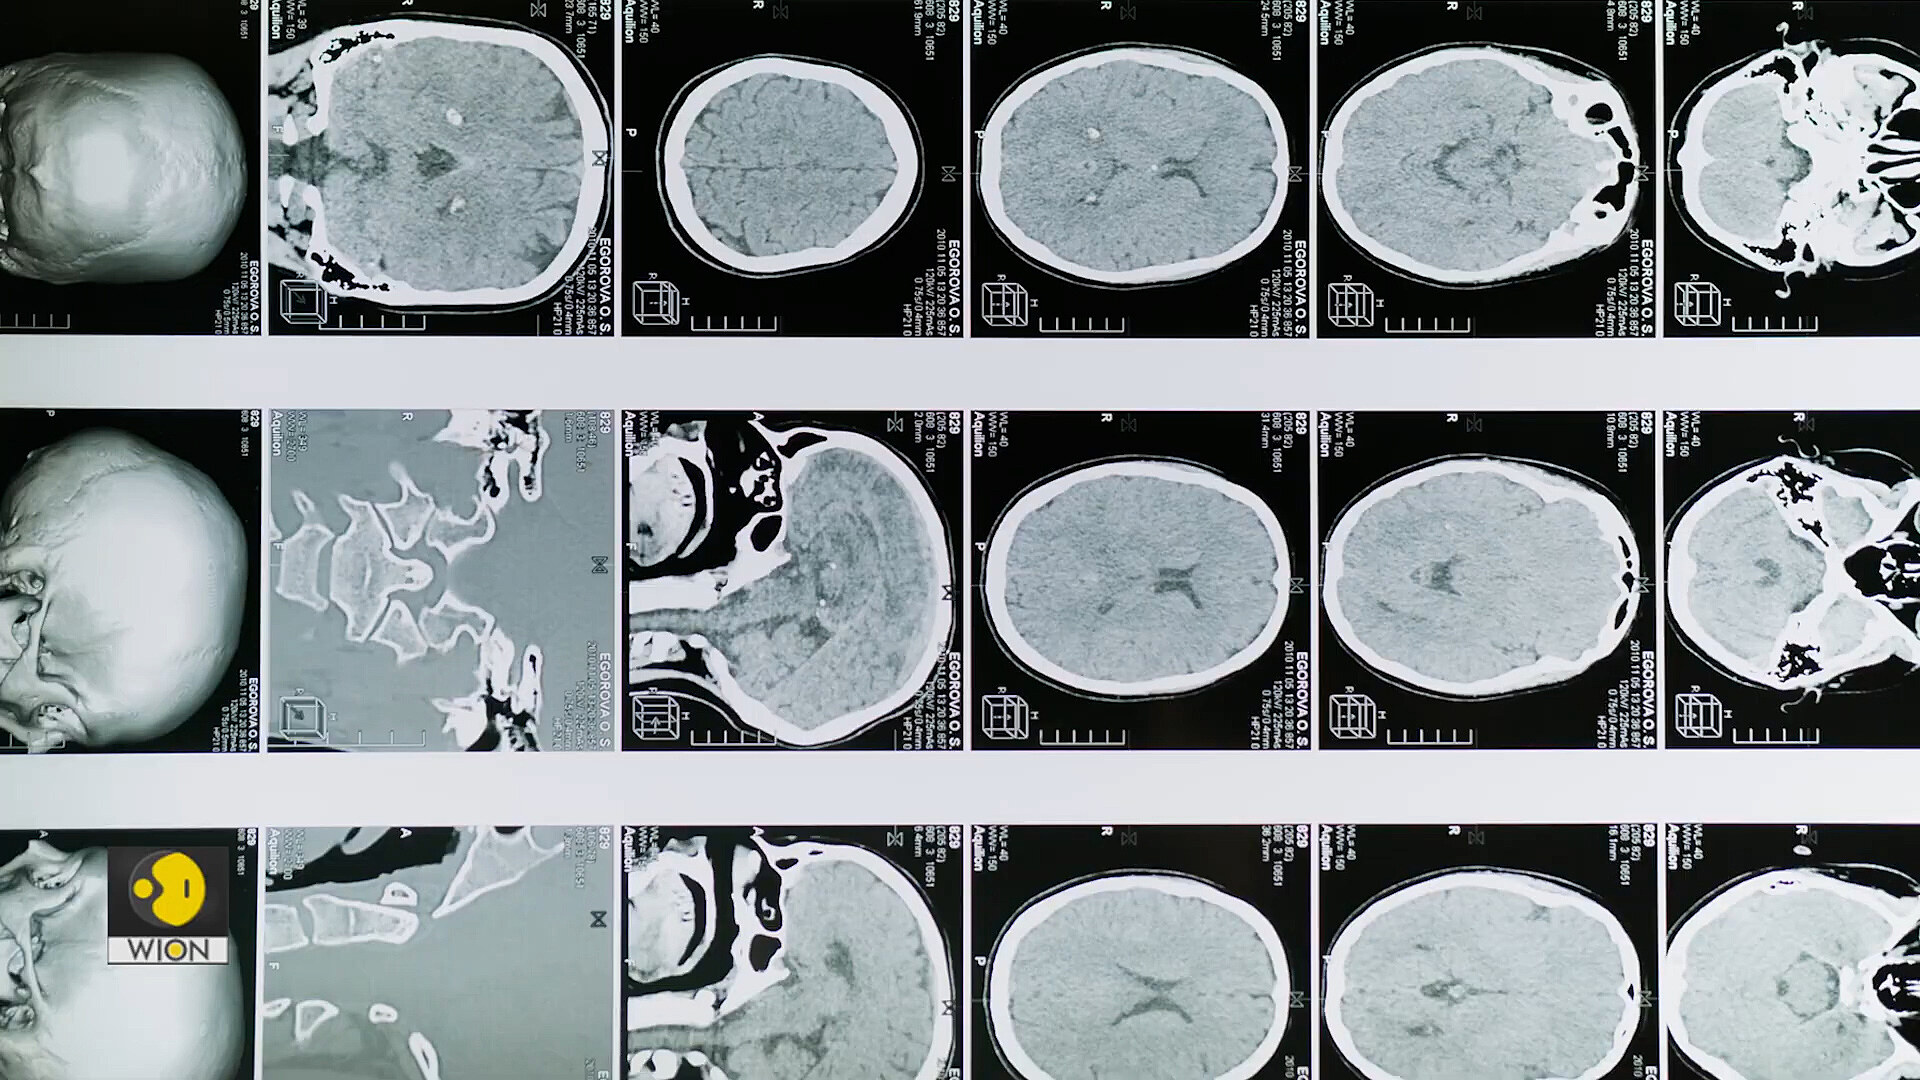

Could gender inequality shrink women's brains? Study explains